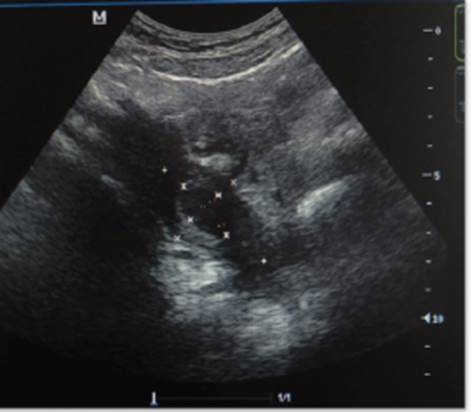

Escolar femenina de 10 años, con antecedente de agenesia renal derecha diagnosticada antenatalmente, quien manifestó dolor pélvico de fuerte intensidad, no asociado a la menarquia. Al examen físico, el abdomen estaba doloroso en hipogastrio y fosa ilíaca derecha, el himen era anular, la vagina estaba permeable. Se practicó ultrasonido pélvico transbadominal 2D y 3D en el cual se apreció el útero doble: el útero derecho con imagen anecoica en su interior, el útero izquierdo de aspecto normal, sin colecciones vaginales (Figura 4).